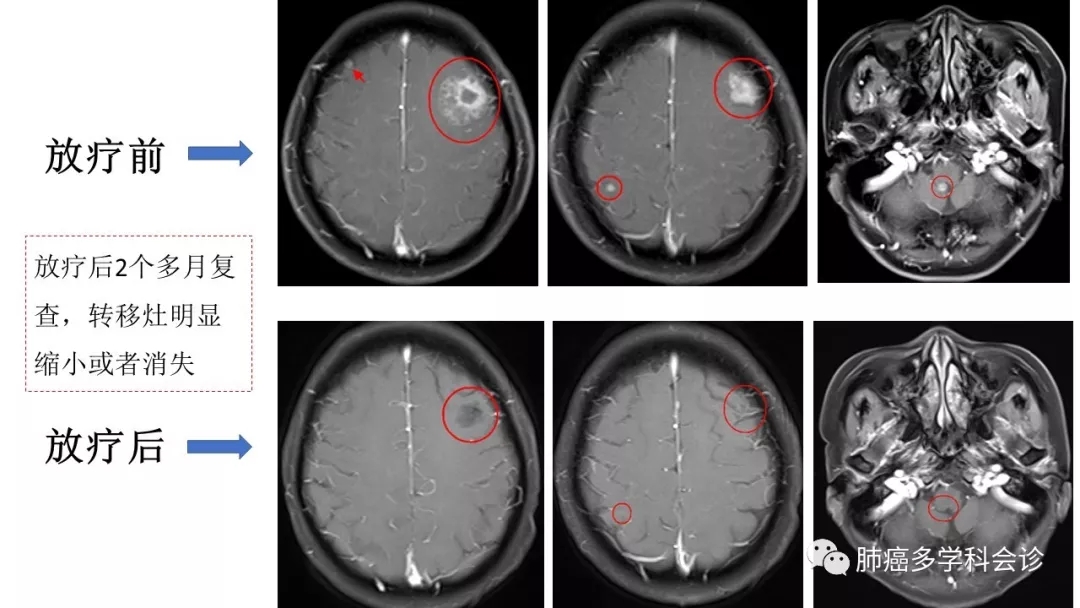

• SRS:(Stereotactic RadioSurgery)立体定向放射外科,应用高度精准的放疗技术,使放射线聚焦在肿瘤部位,病灶受到高剂量照射的同时,最大程度地减少周围正常组织的损伤。一次性完成治疗剂量,像外科手术样去除肿瘤,所以称为放疗“刀”, SF-SRS (single-fraction SRS)